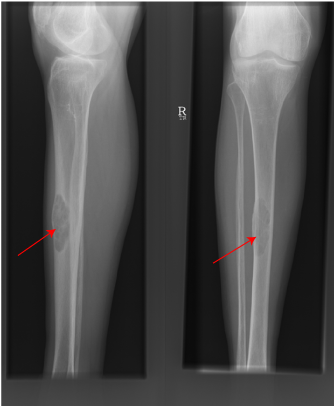

Brown Tumour of Tibia due to hyperparathyroidism

Bone disease (low bone density and osteoporosis) is common but less frequently associated with fractures than in the past. As bone disease may only present clinically and radiologically at an advanced stage, bone densitometry of cortical bone is required to demonstrate osteoporosis in patients with general aches in the context of pHPT.